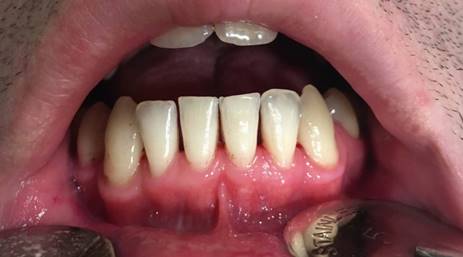

Se reporta el caso de un paciente de sexo masculino, 34 años, sin enfermedades sistémicas conocidas al momento de la primera consulta. No consume medicamentos, no es fumador. Acude en Julio de 2018 derivado por especialista en rehabilitación oral al especialista en periodoncia en la Clínica Odontológica CODUC de la UC. El paciente aceptó la publicación de este caso clínico a través de la firma de un documento de consentimiento informado institucional. El paciente manifestaba un aumento de volumen de la encía de características inflamatorias que comprometía encía marginal, adherida y papilas y que cubría tres cuartos de la corona clínica desde el diente 4.4 al 3.3 (Figura 1). A nivel radiográfico no se observaron efectos de la lesión gingival sobre el tejido óseo ni dientes comprometidos (Figura 2). Al examen clínico el tejido gingival presentaba sangramiento al sondaje sin sintomatología dolorosa asociada. A nivel periodontal se detectó pérdida de inserción periodontal de 1 a 3 mm en el sector de molares. La profundidad al sondaje varió entre 2 y 3 mm. Dada la gravedad de la enfermedad y sospecha de lesión neoplásica no se realizó un registro detallado de nivel de inserción ni profundidad al sondaje de todos los sitios periodontales. Debido a las características clínicas y ubicación de la lesión, la hipótesis diagnóstica pre-quirúrgica planteada fue de un fibroma odontogénico periférico. Dado el alto compromiso inflamatorio y sangramiento asociado, se le indicó al paciente Amoxicilina 1 gramo asociado a Metronidazol 500 miligramos, cada 12 horas durante 7 días con el propósito de reducir la inflamación e infección antes de la cirugía. Luego de dos semanas la lesión no cambió en sus aspectos inflamatorios. Como tratamiento, se decidió la eliminación quirúrgica de la lesión y su análisis mediante histopatología. El examen histopatológico mostró una lesión inflamatoria con gran infiltración por polimorfo nucleares neutrófilos, células gigantes multinucleadas y vasos sanguíneos dilatados asociados a hemorragia (Figura 3). Se solicitó una evaluación de la bioquímica sanguínea, la cual no entregó alteraciones compatibles con neoplasia maligna. El examen histopatológico se realizó en paralelo con el estudio de lesiones inflamatorias que estaban presentes en las fosas nasales por un especialista otorrinolaringólogo, quien detectó pólipos nasales. El paciente finalmente se derivó a un especialista en reumatología quien realizó el diagnóstico definitivo de Granulomatosis de Wegener (GPA) luego del examen clínico y determinación del examen ANCA a nivel sanguíneo. El paciente fue tratado con metotrexato y corticoesteroides. Luego de 2 años el paciente se encuentra sano, sin manifestaciones del Wegener en los tejidos periodontales (Figura 4).